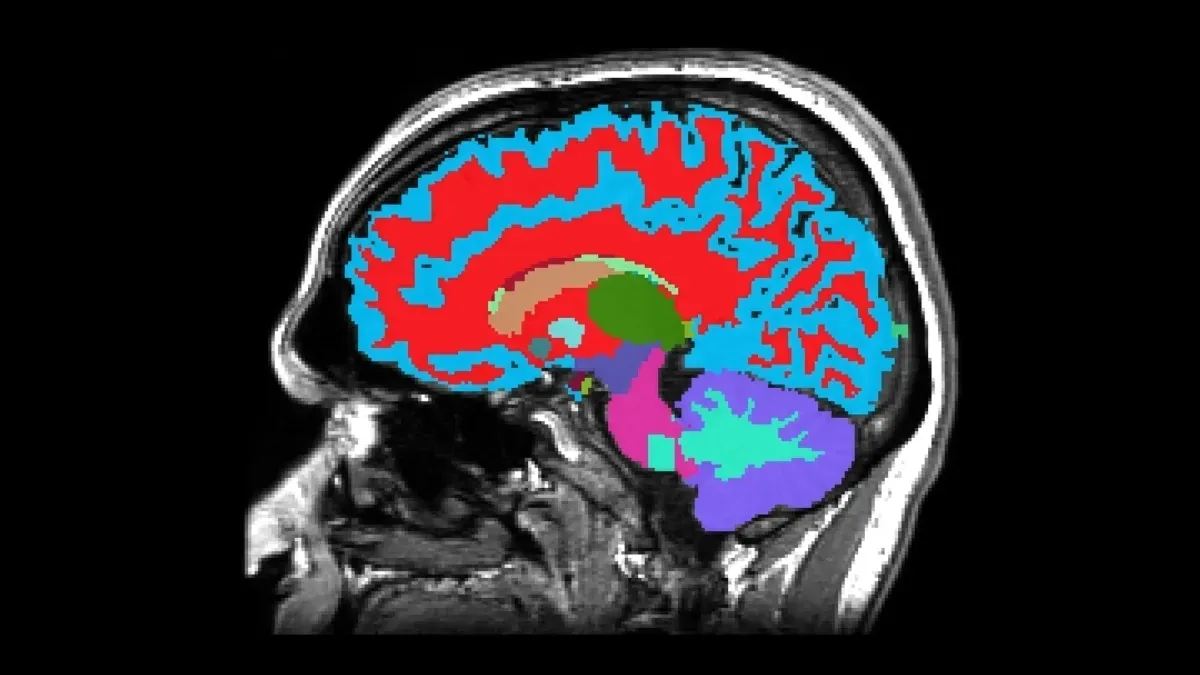

تصویر مغز شما میگوید چه قدر سریع پیر میشوید

ابزار جدیدی که با استفاده از «تصویربرداری رزونانس مغناطیسی» (MRI: Magnetic Resonance Imaging) توسعه یافته، این امکان را فراهم میکند تا تنها از طریق یک تصویر مغزی، شاخصهایی مرتبط با پیری شناسایی شود. این مدل با بهرهگیری از الگوریتمهای «یادگیری ماشین» (machine learning) میتواند سرعت پیری یک فرد را بر اساس ویژگیهای ساختاری مغز، از جمله حجم ماده خاکستری، ضخامت قشر مغز (cortex) و سلامت «هیپوکامپ» (hippocampus)، برآورد کند.

هیپوکامپ که نقشی کلیدی در حافظه و یادگیری دارد، یکی از نخستین مناطقی است که در بیماریهای نورودژنراتیو مانند «آلزایمر» (Alzheimer's disease) دچار تحلیل میشود. کاهش زودهنگام در اندازه این بخش از مغز، حتی پیش از بروز اختلالات شناختی آشکار، میتواند نشانهای از تسریع در روند پیری عصبی باشد. این کشف به پژوهشگران اجازه داده تا به جای واکنش به بیماری در مراحل پیشرفته، به پیشبینی و پیشگیری بپردازند.

دقت این مدل درگرو دادههای غنی مطالعه «دوندین» (Dunedin Study) است؛ پژوهشی طولی که بیش از هزار نفر را از زمان تولد در دهه ۱۹۷۰ در نیوزیلند تا میانسالی و کهنسالی دنبال کرده است. این مطالعه نهتنها اطلاعات زیستی، بلکه دادههای روانشناختی، اجتماعی و رفتاری را نیز در اختیار پژوهشگران قرار داده است. مدل مذکور با استفاده از اسکن MRI افراد در سن ۴۵ سالگی و دادههای زیستی ۲۰ سال گذشته آنان، الگوریتمی را شکل داده که میتواند «شتاب پیری» را با دقتی قابل قبول پیشبینی کند.